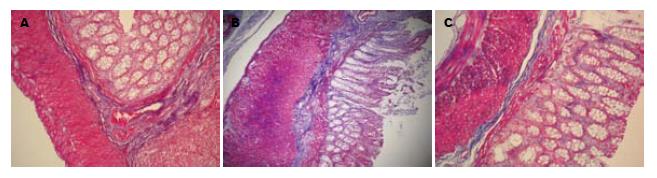

各组大鼠结肠组织HE染色(×200).

A: 正常对照组; B: 模型组; C: 大黄素组.